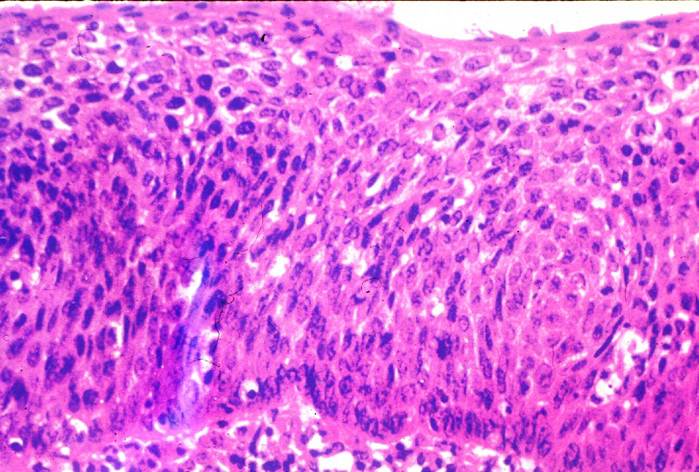

cervix